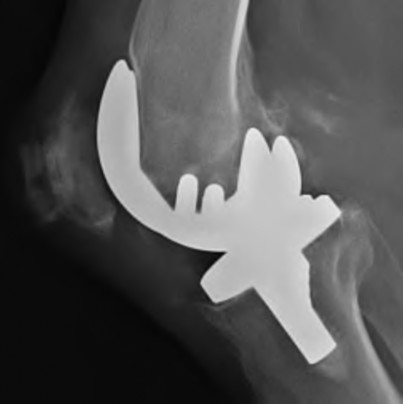

A 72-year-old female presents with progressive left thigh and knee pain for the last year. 5 years ago she sustained a femoral neck fracture treated with the implant seen in Figures A-C (current radiographs). The thigh pain is worse with weight-bearing. C-reactive

protein and erythrocyte sedimentation levels are within defined limits. Which of the following is the most likely cause of her pain?